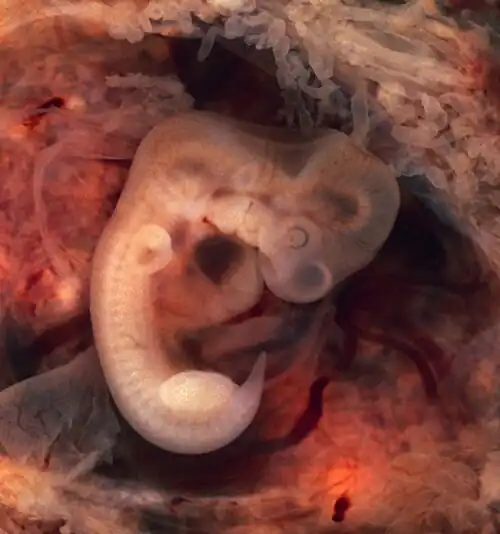

Image of a human embryo at 7th weeks of gestational age. doi: 10.15347/WJM/2014.007